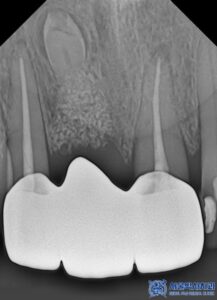

신경치료를 마무리 한 후에는

지르코니아 브릿지 크라운을 제작하였습니다.

치료 마무리 후 사진입니다.

치료 후 환자분께서 거울을 보시면서

이렇게 자연스럽게 치료될 줄 몰랐다고 하시며,

임플란트 해야 하는 줄 알았는데 자연치아를

살릴 수 있어서 너무 만족한다고 좋아하셨습니다.